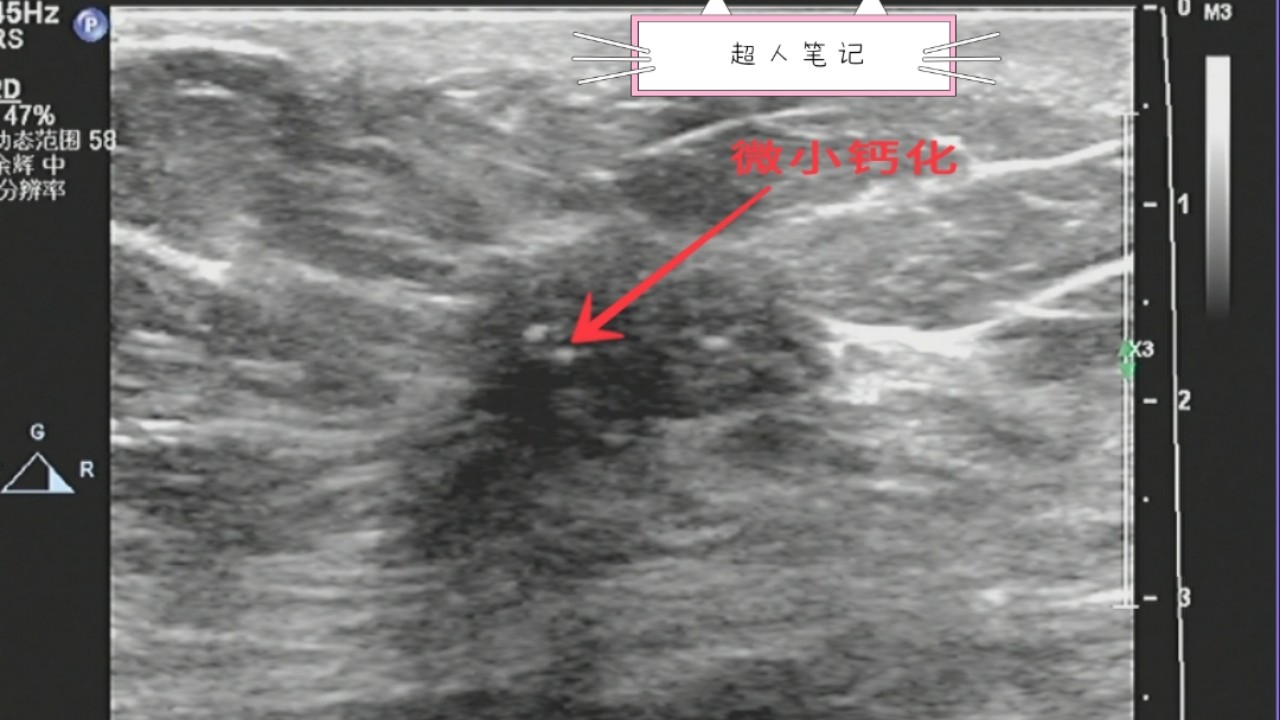

5、有微小钙化。